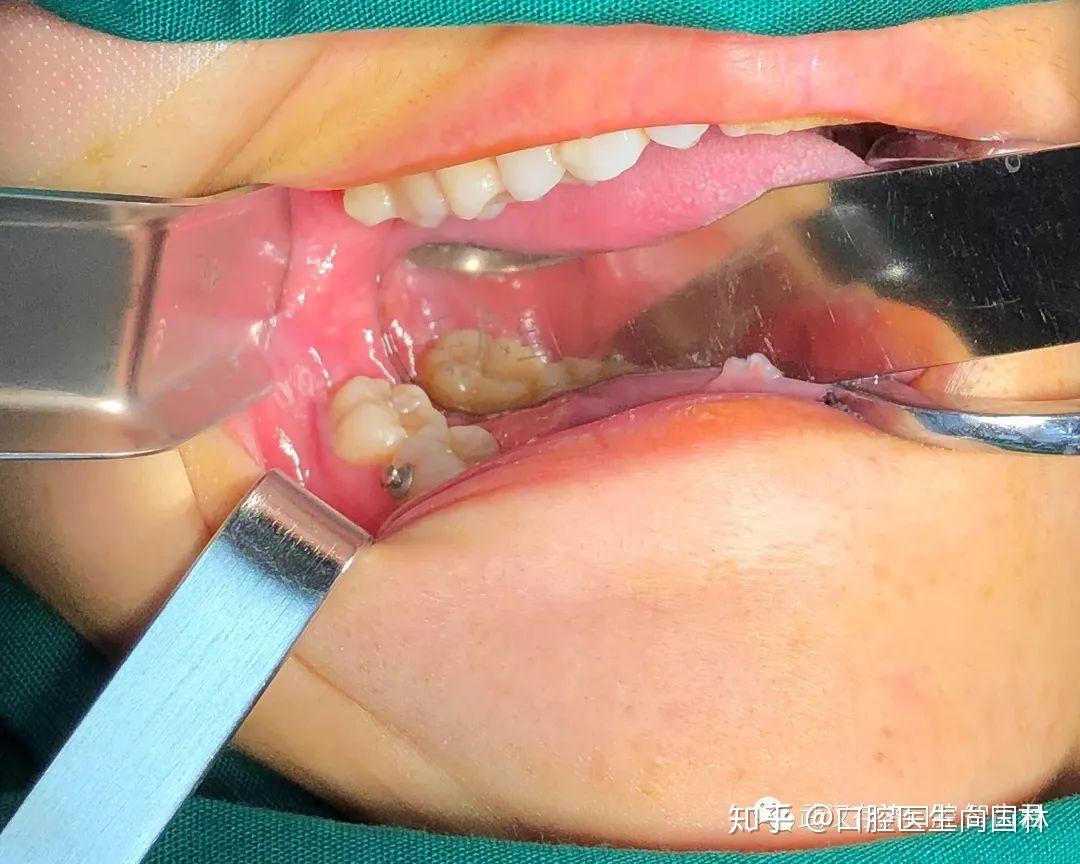

真实案例超声骨刀微创拔除下颌阻生智齿